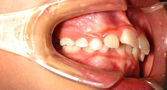

下顎前突(かがくぜんとつ)・受け口

主訴:受け口・前歯部交叉咬合

年齢:7y2m

診断:上顎劣成長による骨格性下顎前突

装置・期間:

第一期治療 上顎拡大+上顎前方牽引装置(クアッドヘリックス+フェイシャルマスク)+バイヘリックス+セクショナルアーチ 6年7カ月間(7y5m~14y0m)

第二期治療 上下顎マルチブラケット装置 3年5カ月間(16y2m~19y7m)

保定 上下顎保定装置 2年間以上

治療費:第一期治療 矯正基本料400,000円+処置料3,000~6,000円×40回(別途消費税)

第二期治療 矯正基本料400,000円+クリアブラケット代30,000円+処置料3,000~6,000円×37回(別途消費税)

保定装置料 55,000円(別途消費税)